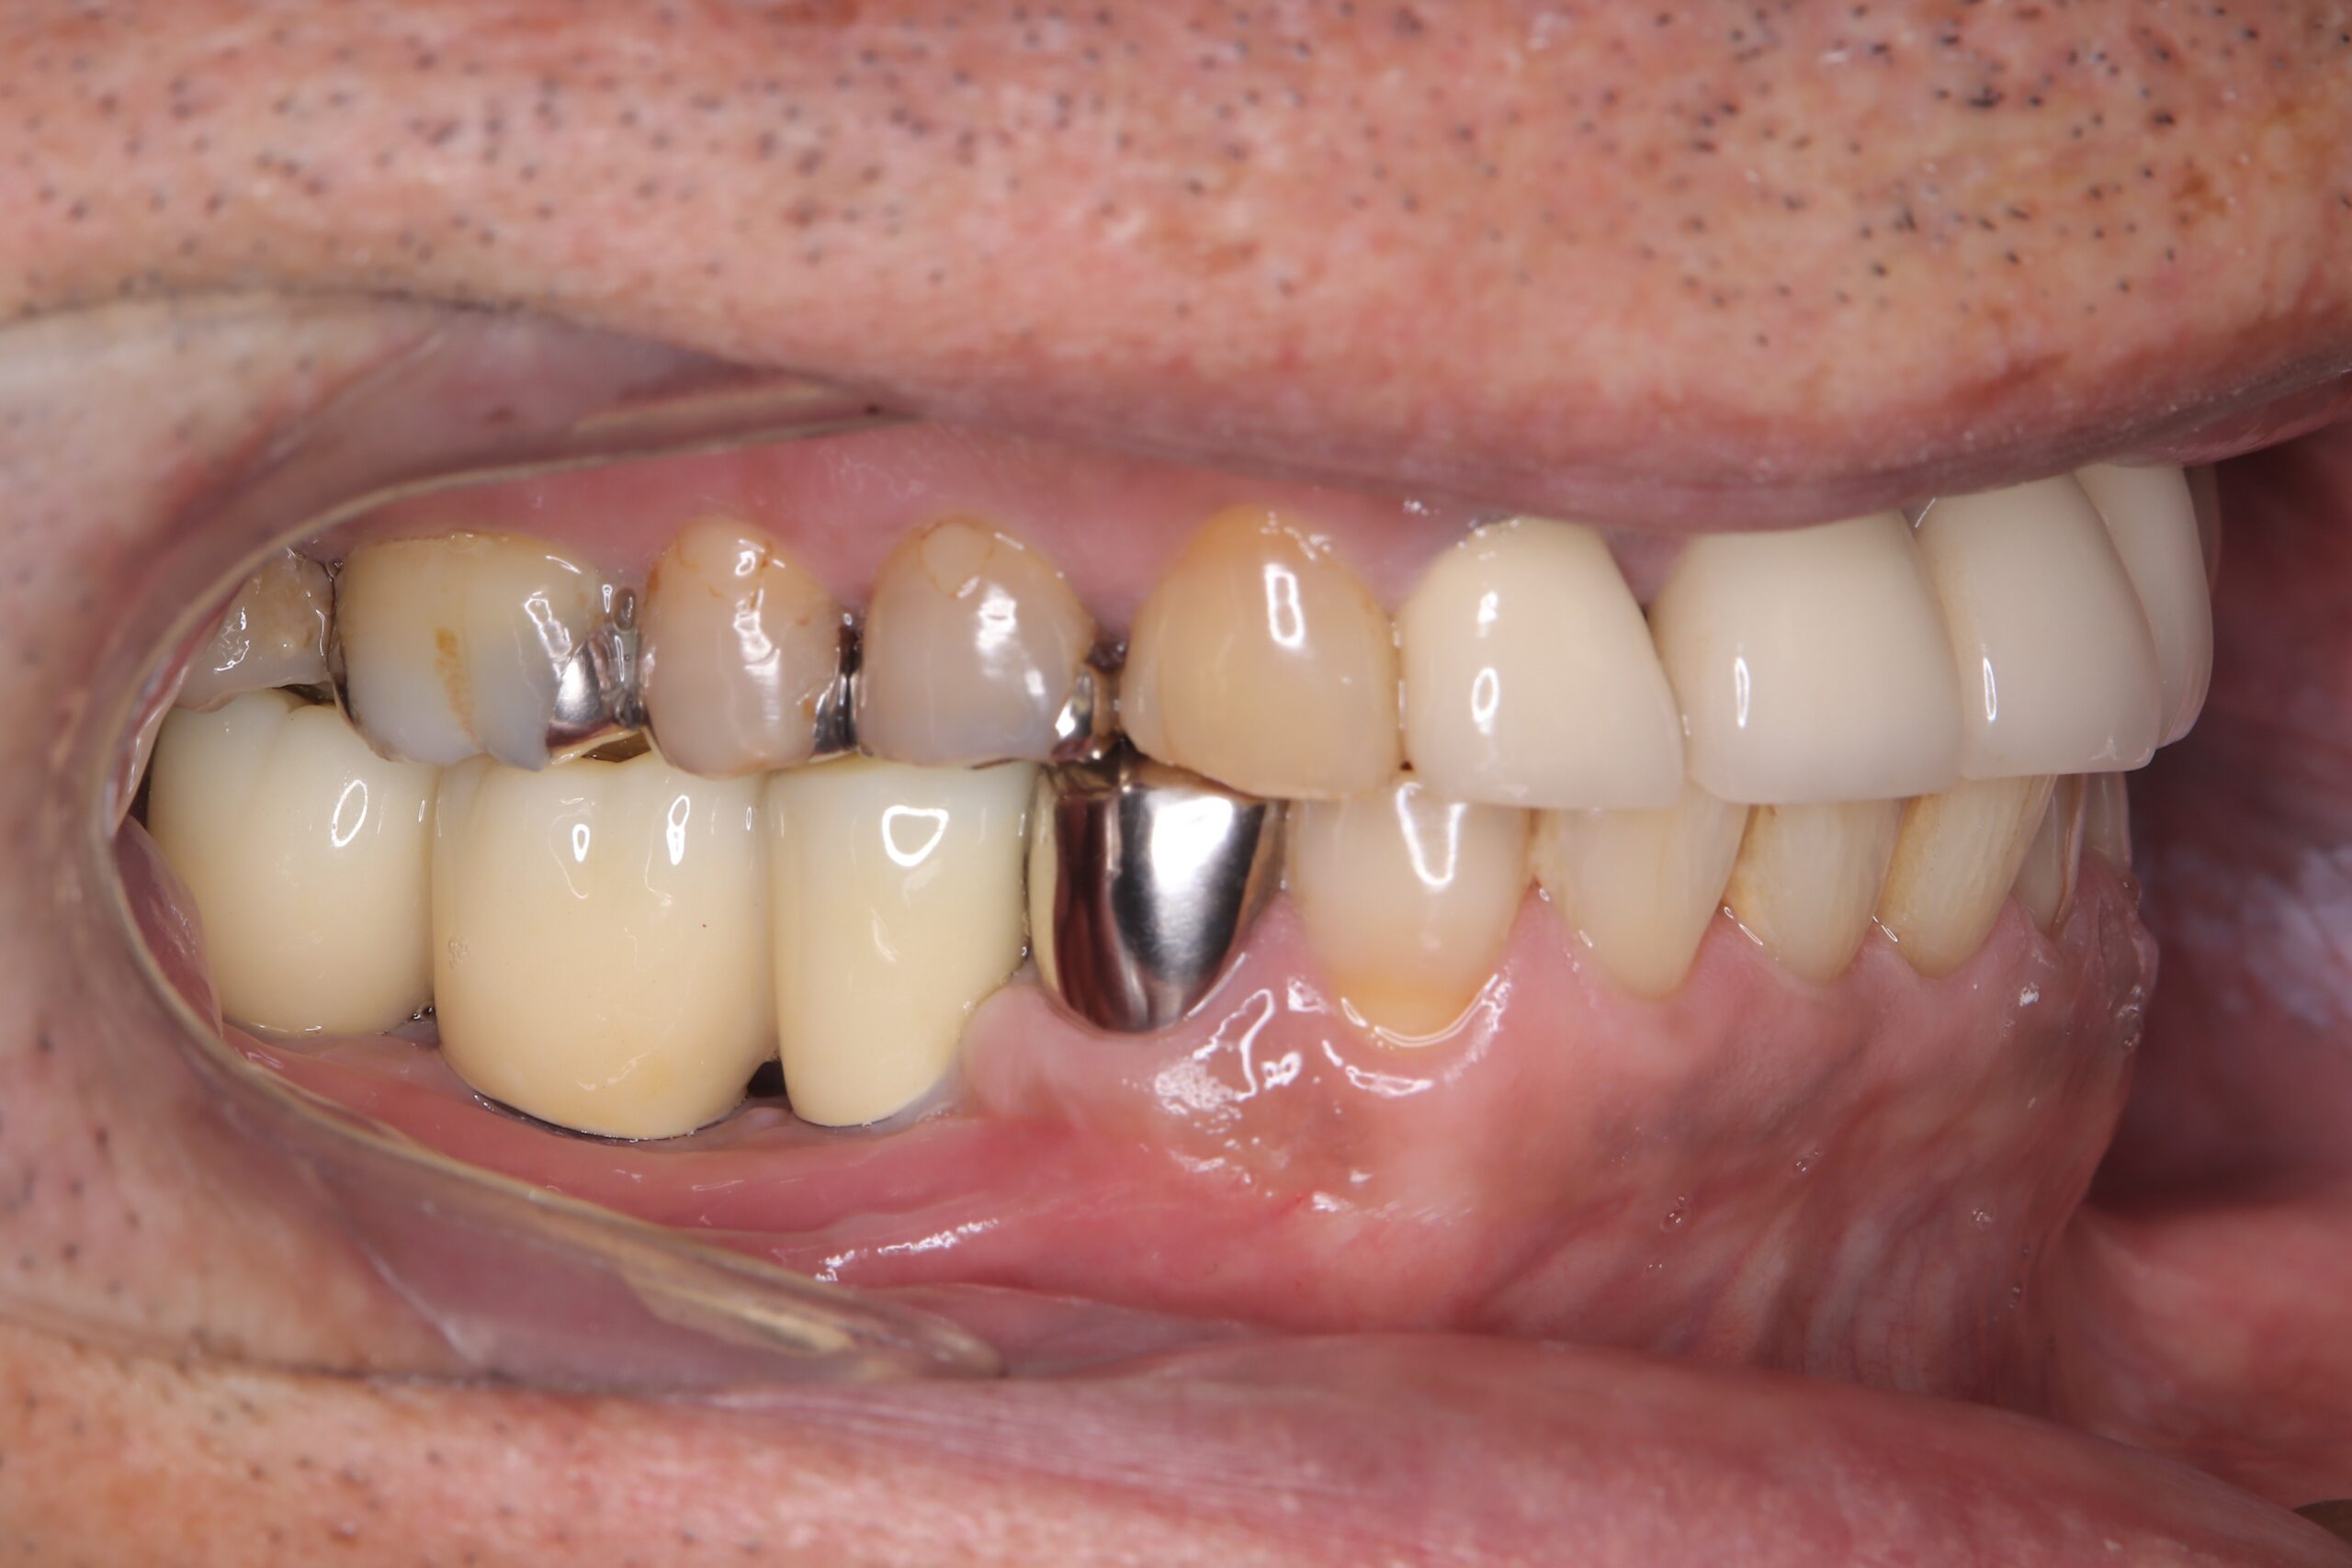

治療前

インプラントに土台を取り付けました。